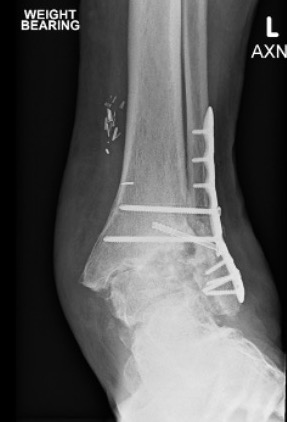

ORIF

Technique

Locking plates

Multiple syndesmotic screws